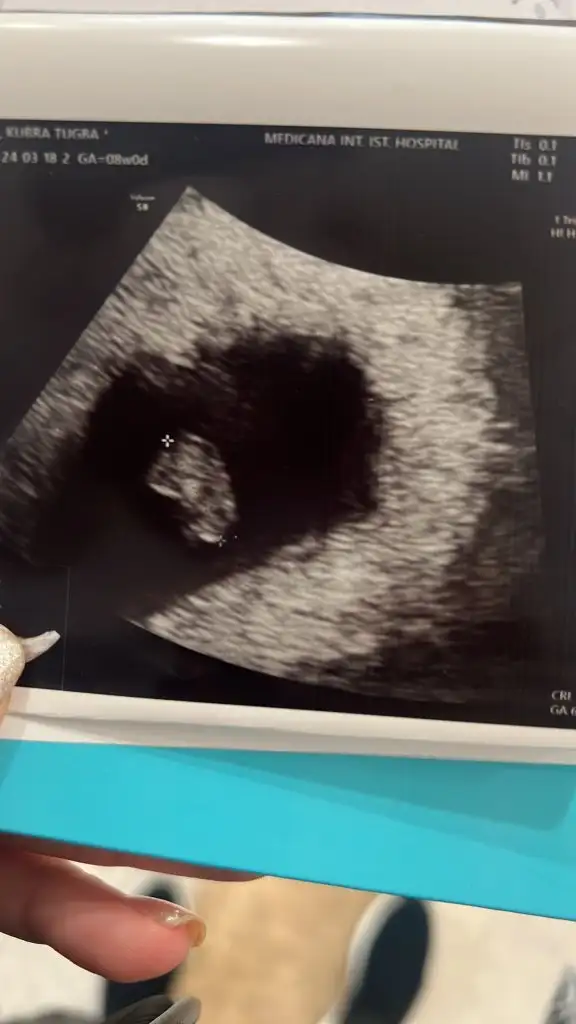

Merhabalar malesef çok güzel haberler le gelemedim devlete randevu almıştım özelde bir ay sonraya çağırdığı için bebeklerimin biri haftasıyla uyumlu 10+1 ama malesef diğeri melek olmuş bile 8+4 de kalbi durmuş çok üzüldüm ama bunda da bir hayır vardır diyorum rabbim bir tane yazmış demekki yazımıza . Belki sağlıklı değildi diyorum ama yine de çok ağladım hep iki diye hayal kurdum ..😞